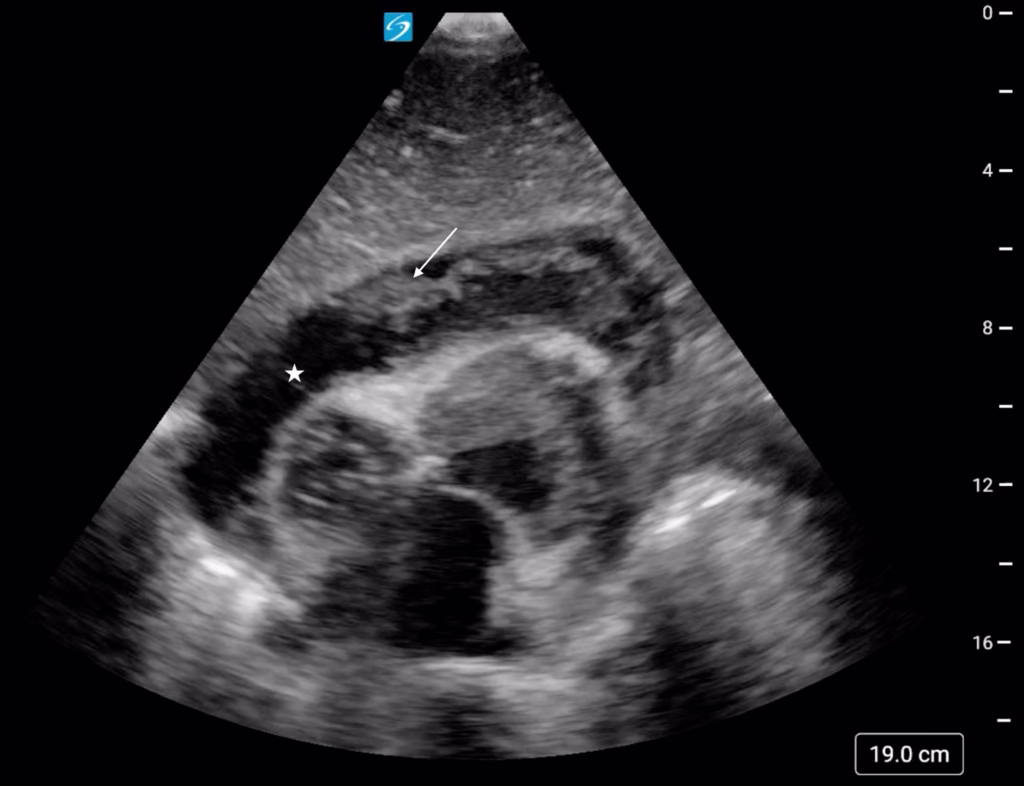

A 44-year-old man with a history of type I diabetes mellitus, cocaine abuse, and alcohol abuse presented to the emergency department (ED) in cardiac arrest after collapsing in the shower. The patient had been complaining of right upper quadrant abdominal pain radiating to the right shoulder for two weeks prior to the event. He received a total of 6 mg epinephrine, 1 g calcium gluconate, 50 mEq sodium bicarbonate, and 2 mg naloxone by emergency medical services (EMS). The patient was intubated prior to ED arrival. Endotracheal tube placement was confirmed prior to and after patient transfer from the EMS stretcher. Mechanical compressions were provided via a Lund University Cardiopulmonary Assist System (LUCAS) device. Upon initial pulse check, a carotid pulse was palpated and return of spontaneous circulation (ROSC) was noted. Initial post-ROSC vital signs were remarkable for hypothermia (33.3°C, axillary), tachycardia (127 beats per minute), and hypotension (66/40 mmHg). During resuscitation, cardiac point of care ultrasound (POCUS) examination was performed which revealed a pericardial effusion with concern for tamponade (Figure 1).

Figure 1. Subxiphoid cardiac point of care ultrasound (POCUS) view demonstrating a mixed echogenicity pericardial effusion (star) with fibrinous strands (arrow).